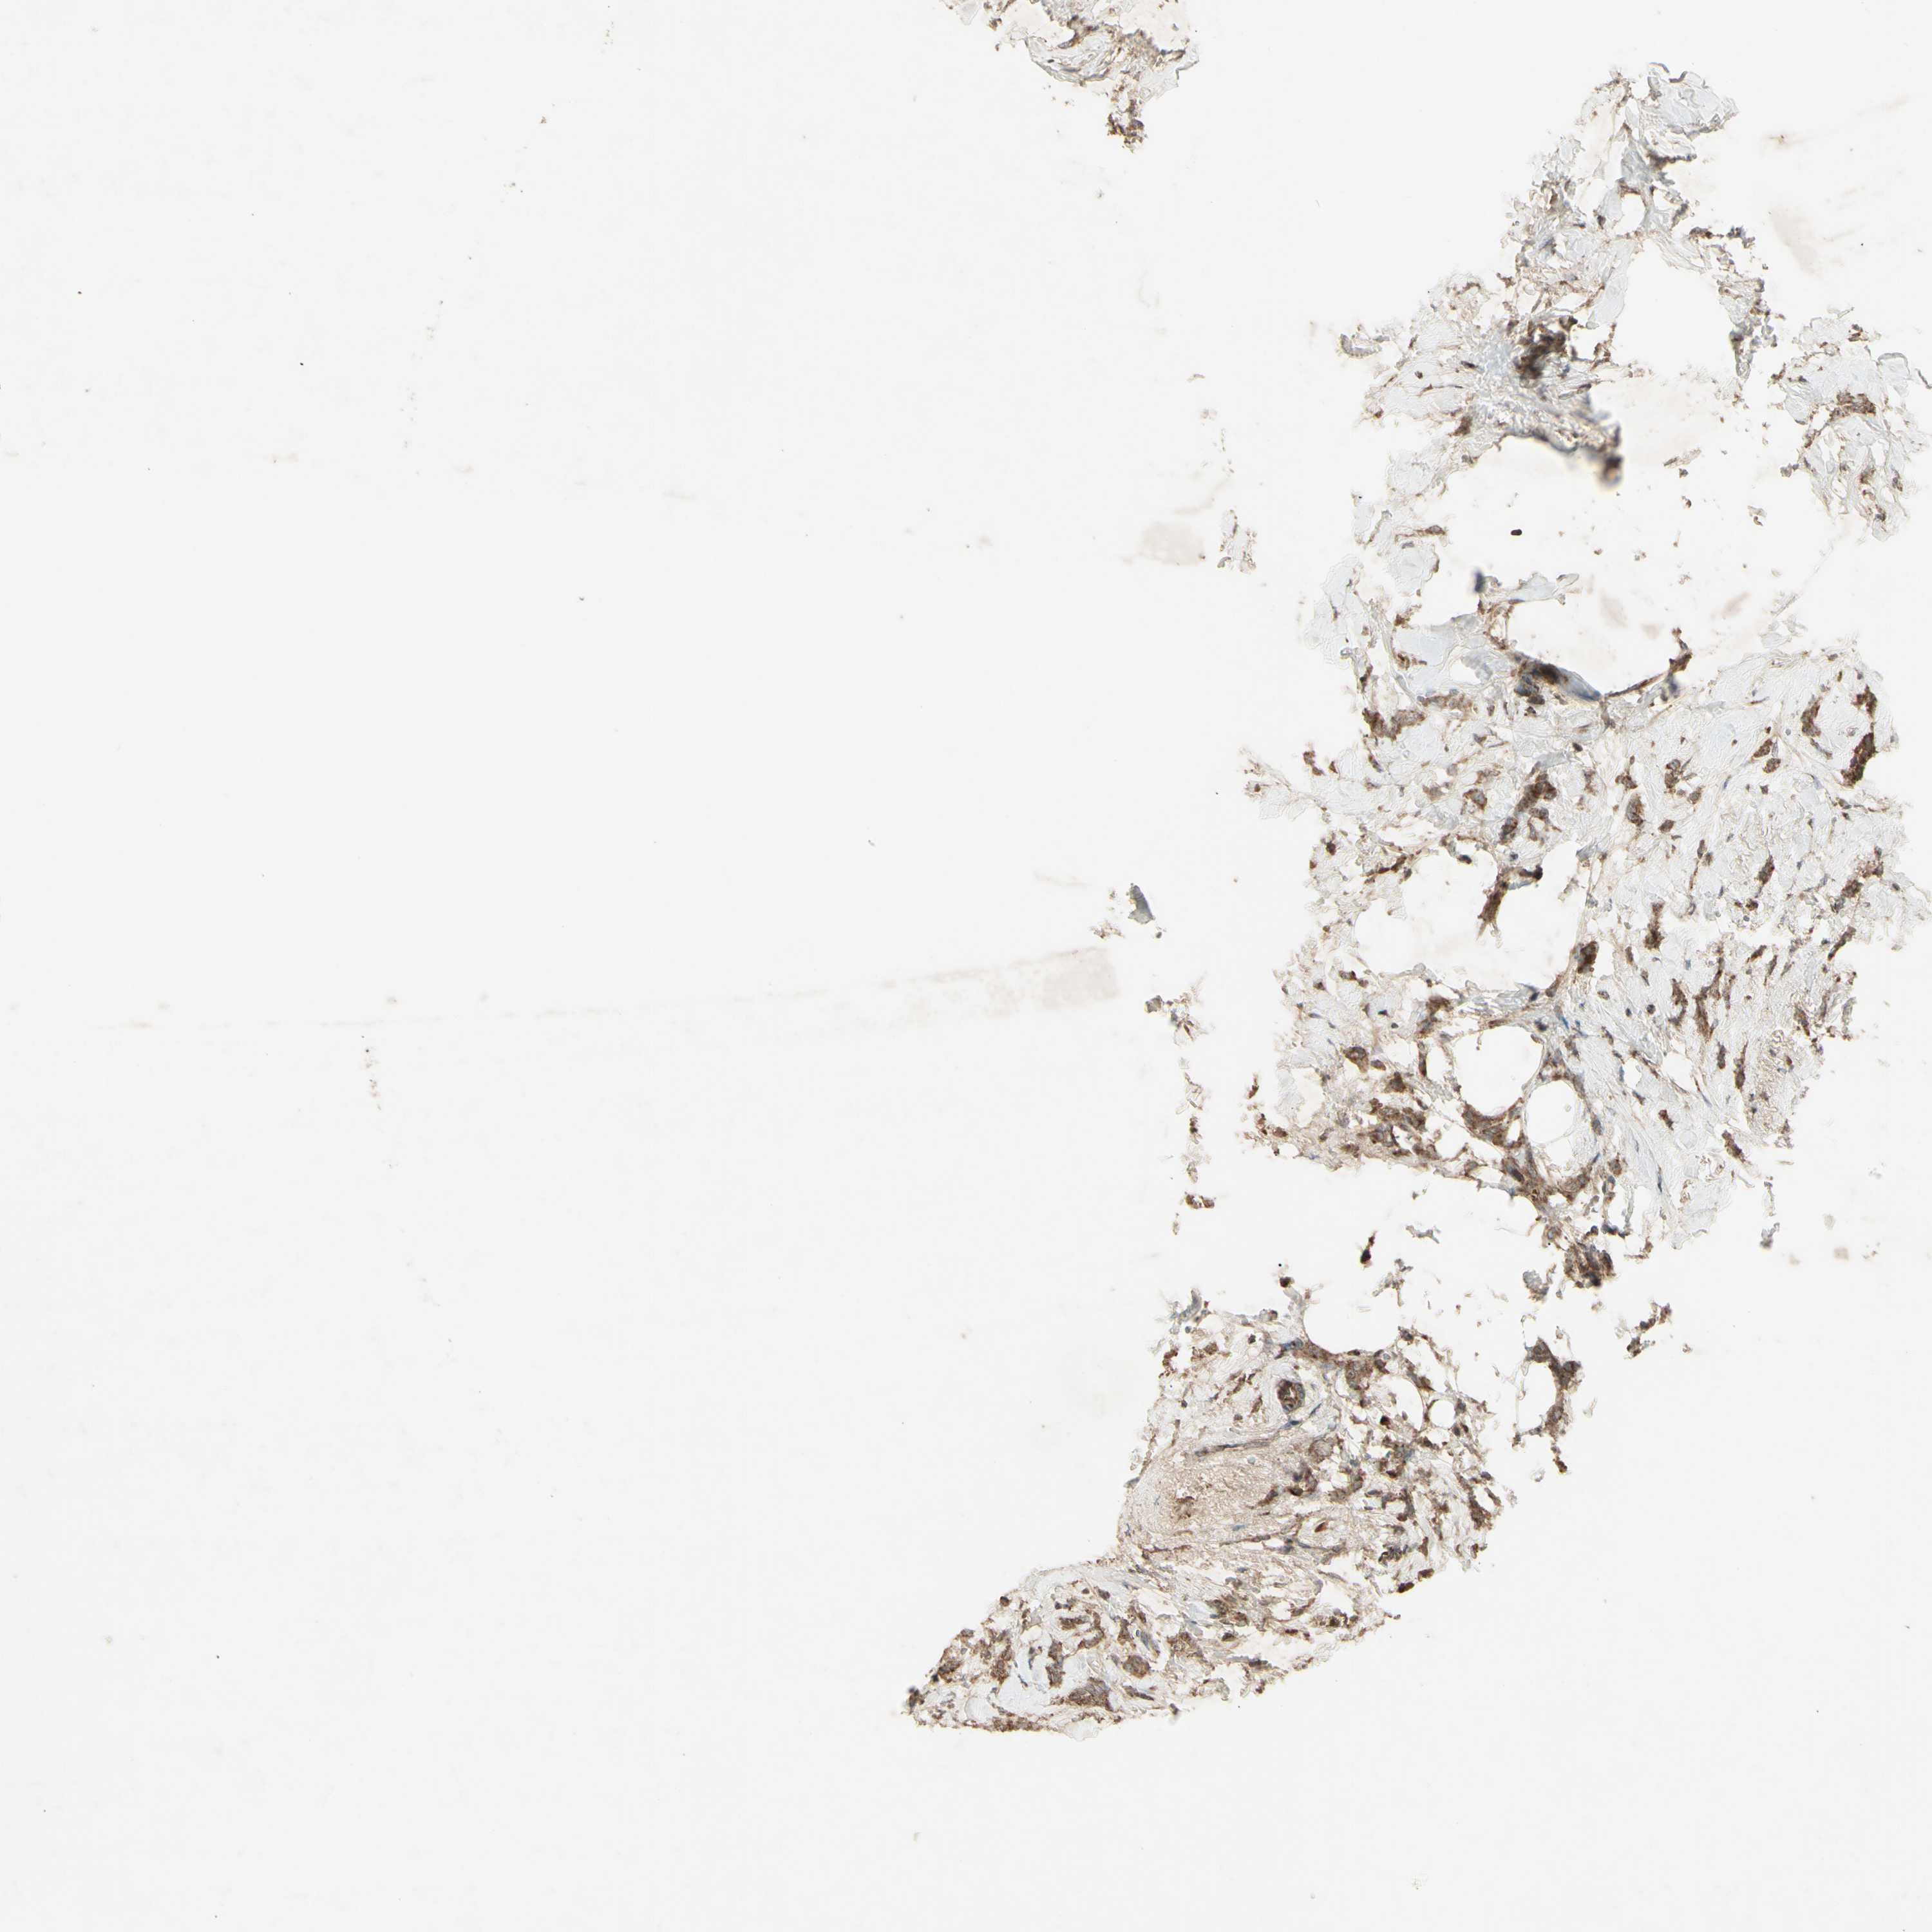

BRCA TCGA BRCA VALIDATION PROTEIN EXPRESSION

Breast cancer

Human cancer